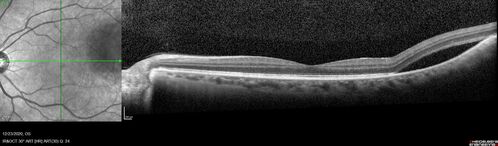

51 year old female.  First 3 sets of images show lesions growing despite systemic chemotherapy.  She eventually had external beam radiation x 15 sessions and the tumors shrunk in the last two sets of images